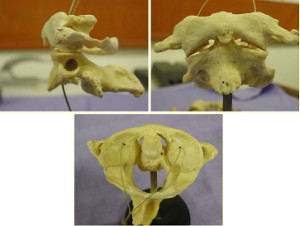

- Surgical management of pelvic primary bone tumors involving the sacroiliac joint. Sabourin M, Biau D, Babinet A, Dumaine V, Tomeno B, Anract P. Orthop Traumatol Surg Res. 2009 Jun;95(4):284-92. doi: 10.1016/j.otsr.2009.04.008. Epub 2009 May 30. PubMed PMID: 19482533.

- Fractures du Sacrum - Rappels anatomiques et classification. Sabourin M, Rousseau MA, Sofia T, Lazennec JY : In Traumatismes de la ceinture pelvienne. Sauramps Medical. 2007.pp 143-150

- Fractures en U du sacrum - Mécanisme physiopathologique et expérience de la Pitié. Sabourin M, Rousseau MA, Sofia T, Lazennec JY, Bendaya S In Traumatismes de la ceinture pelvienne. Sauramps Medical. 2007. pp 151-160